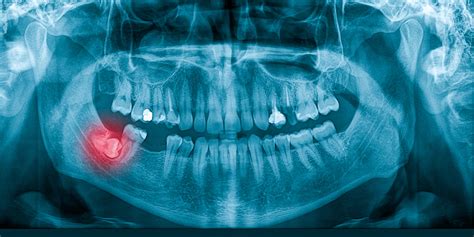

Síntomas y Diagnóstico

Es importante destacar que algunos dientes retenidos pueden no causar síntomas notorios y pueden ser descubiertos durante un examen dental de rutina. Los dientes retenidos suelen ser asintomáticos, se pueden detectar en las visitas de rutina al dentista y con radiografías.

El diagnóstico de los dientes retenidos se inicia con un examen clínico, en tu visita al dentista este evaluará tus síntomas y mirará la posición de tus dientes. El diagnóstico precoz es clave para determinar la causa y planificar un tratamiento adecuado.

- Examen radiográfico: incisivo central superior derecho cerca de la espina nasal anterior, situado perpendicularmente al plano oclusal.